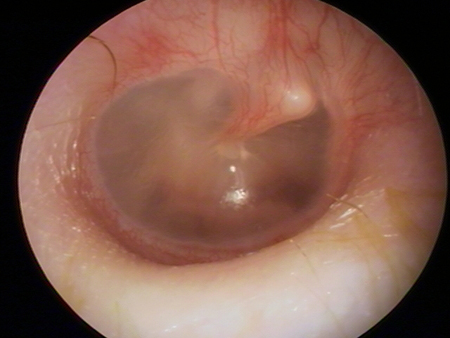

Otitis media with effusion

Otoscopy of myringitis, showing erythema and injection of the tympanic membrane in the neutral position

From the personal collection of Dr Armengol